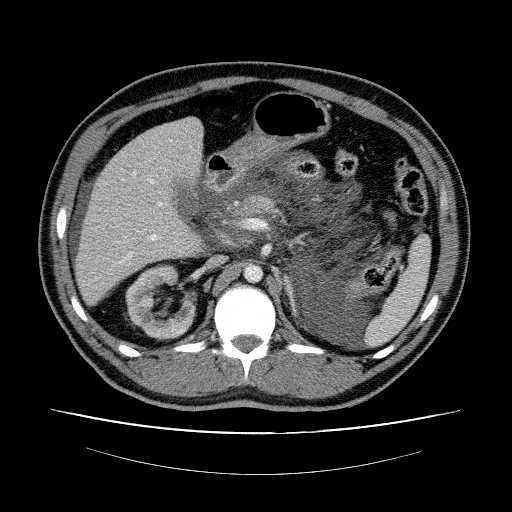

En la exploración física destacaba epigastralgia marcada. Recuento celular : 50 leucocitos (65% PMN), amilasa 423 UI. Otros datos analíticos: Leucocitosis 25700 (92% de neutrófilos), Urea 106 mg/dl, Creatinina: 9,4 mg/dl, PCR: 24 g/l, Amilasa: 173 UI/l. Cultivos de líquido peritoneal negativos. Ante la presencia en líquido peritoneal de amilasas > 100 UI/l y la sospecha clínica de pancreatitis se efectuó TAC abdominal : Rarefacción de grasa peripancreática y gran cantidad de líquido libre fundamentalmente peripancreático y perihepático. (Figura 1). Inicialmente evolucionó favorablemente. Se mantuvo en diálisis peritoneal y se descartaron causas metabólicas o infecciosas de la pancreatitis. 4 días después del ingreso el paciente presentó fiebre, y líquido peritoneal con más 100 leucocitos ( 80% PMN / Amilasas < 100 UI). Ante los antecedentes de una peritonitis previa por Staph. Epidermidis con recaída posterior, se decidió retirar catéter peritoneal y transferir a hemodiálisis. La evolución posterior fue favorable, con desaparición de la fiebre y mejoría clínica.

Tabla Figura 1.